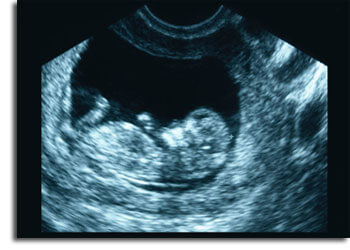

Ultrasound

Ultrasound (also called sonography) is a diagnostic medical procedure that uses high-frequency sound waves to produce dynamic visual images of organs, tissues or blood flow inside the body. The high-frequency sound waves are transmitted to the area of interest and the returning echoes recorded. This type of procedure is often referred to as a sonogram or ultrasound scan. Selected images are used by an interpreting physician to make a final diagnosis.